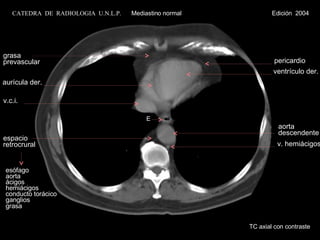

TC axial con contraste E v.c.i. ventrículo der. grasa prevascular pericardio esófago aorta ácigos hemiácigos conducto torácico ganglios grasa espacio  retrocrural aurícula der. aorta descendente v. hemiácigos CATEDRA  DE  RADIOLOGIA  U.N.L.P.   Mediastino normal  Edición  2004

TC axial concontraste E v.c.i. ventrículo der. grasa prevascular pericardio esófago aorta ácigos hemiácigos conducto torácico ganglios grasa espacio retrocrural aurícula der. aorta descendente v. hemiácigos CATEDRA DE RADIOLOGIA U.N.L.P. Mediastino normal Edición 2004